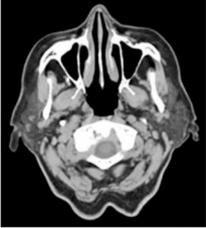

A CT előnye a lágy és kemény szövetek direkt elkülönítése és a lágy szövetek denzitásbeli finom különbségeinek kimutatása. A jóindulatú daganatok a CT-képeken általában, mint élesen körülhatárolt tumorok jelennek meg, többnyire hiperdenzek a környezethez viszonyítva. A malignus elváltozások rosszul körvonalazottak, a mirigy határain túl terjedhetnek, de a CT-kép alján pontosan nem differenciálhatók. (Kivételek a lyphomák, liposarcomák és a haemangiomák, a zsírra jellemző denzitás és a kontrasztanyag fokozott dúsítása révén). A submandibularis mirigy esetében a denzitásbeli különbség kisebb volta a kórismét nehezítheti, de a kép az ellenoldali miriggyel való összehasonlítása a különbséget kimutatja, kétséges esetben szialográfiás eljárással kombinálva világosan körülrajzolható a daganat. A CT legfontosabb indikációja, amikor a nyálmirigyen belüli szövetszaporulat extrinsic vagy intrinsic volta pontosan nem ítélhető meg. Ekkor a választandó sebészi beavatkozás irányát is befolyásolhatja a radiológiai lelet. Lehetővé teszi a nyálmirigyek és az azokat határoló lágyszövetek közötti finom különbségek, a mirigyeken belül elhelyezkedő tumorok határainak pontos megítélését; intravénás kontrasztanyagot használva ér eredetű malformációk vizsgálatát, illetve szialográfiával kombinálva a térfoglaló folyamatok kiterjedésének pontosabb lokalizációját (12.4. ábra).

12.4. ábra. Ép parotis natív

(Dr. Kollár József anyagából)